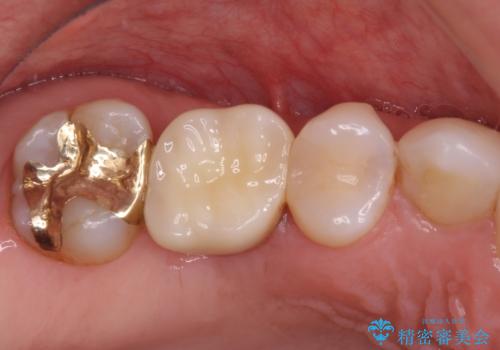

- 奥歯の銀歯をセラミックにしたいとのことで来院された患者様です。

より白さが目立つように、自然な仕上がりではなく、作り物の雰囲気があるフルジルコニアクラウンにて補綴治療を行いました。